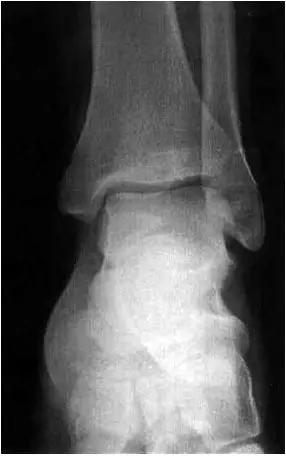

男,11岁,自述后踝下方疼痛,活动时为甚,并有一突起。

2、影像学表现:

- 踝关节正侧位X 线平片,侧位片均显示距骨后方有三角形或椭圆形的距后三角骨。部分病例伴有轻度的踝关节骨性关节病。